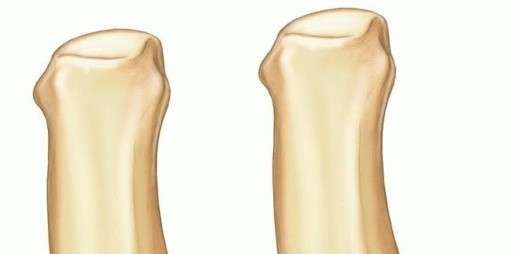

Osteology and Articular Kinematics

The osseous architecture of the thumb CMC joint is inherently unstable without its soft tissue envelope. The articular surface of the trapezium is saddle-shaped, articulating with the reciprocally shaped base of the first metacarpal. During palmar abduction, the metacarpal base glides dorsally on the trapezium, while during adduction, it glides volarly. Flexion and extension involve a complex rolling and gliding mechanism along the orthogonal axis. This intricate kinematic dance means that any articular step-off greater than 1 millimeter will drastically alter contact pressures, leading to point loading, accelerated cartilage wear, and inevitable early-onset osteoarthritis.

Fracture Patterns and Buchler Zones

These deforming forces lead to classic intra-articular fracture-dislocation patterns. The Bennett Fracture is a two-part intra-articular fracture where the metacarpal shaft is radially and dorsally displaced by the pull of the APL. Crucially, a small, intact ulnar fragment remains at the base of the thumb metacarpal, held perfectly reduced by the strong volar beak ligament. The Rolando Fracture represents a more complex, comminuted intra-articular fracture involving the base of the thumb metacarpal, classically presenting as a T or Y-type pattern. By definition, no portion of the metacarpal shaft remains in continuity with the CMC joint, rendering it profoundly unstable.